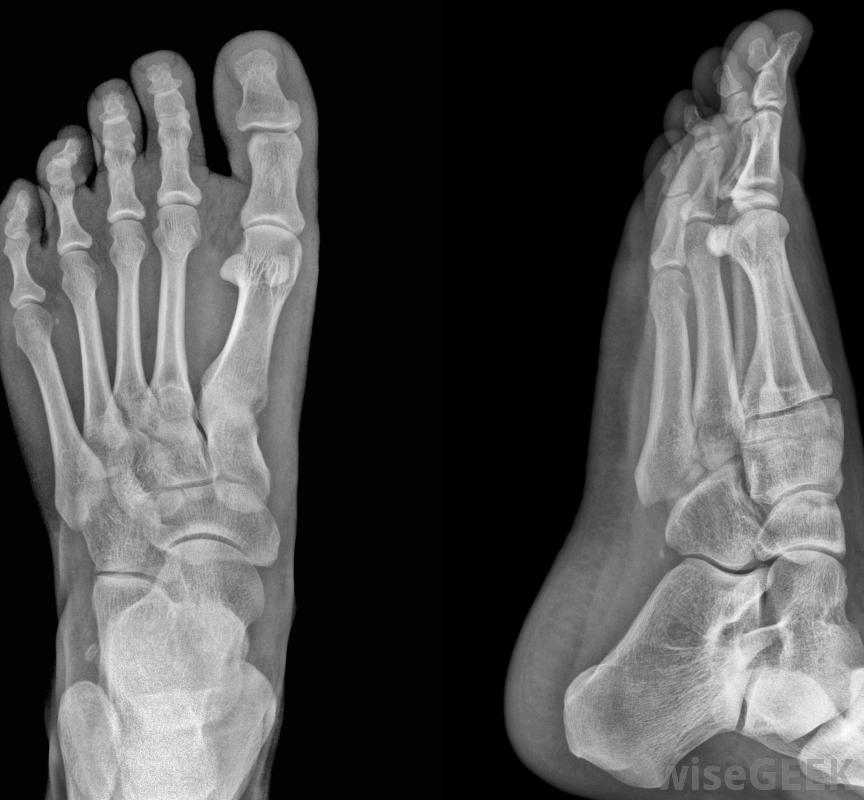

x光片可以用来检查囊肿。